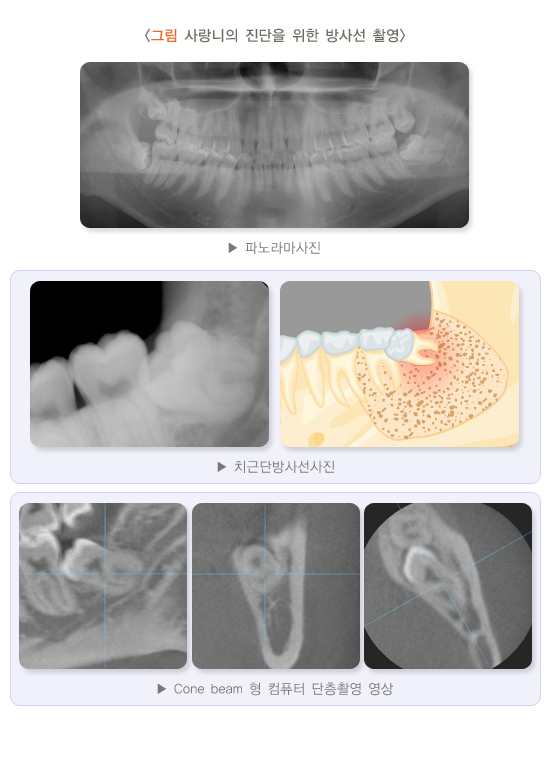

파노라마 사진과 치근단 엑스레이 필름을 촬영하여 전반적인 환자의 치아와 턱뼈의 상태를 확인합니다. 하악관과 가깝거나 치근이 심하게 구부러진 경우 등 비정상적인 상태라면 치과용 컴퓨터단층촬영(computed tomography, CT)을 추가로 시행합니다.

5. 사랑니의 진단을 위한 방사선 촬영

치과용 엑스레이는 전체 치아 및 턱뼈의 전반적인 평가가 필요할 때 찍는 파노라마 사진과 치아 한두 개를 잘 관찰하기 위해 찍는 치근단방사선 사진이 있습니다. 아래턱 사랑니 치근 아래쪽으로 하치조 신경이 포함된 하악관이 지나가는데 파노라마 사진을 통해 하악관의 대략적인 위치와 사랑니를 포함한 전체 치아 및 잇몸뼈의 상태를 평가할 수 있습니다. 아래턱 사랑니가 신경관에 아주 근접해 있다면 발치 후 일시적으로 하치조 신경이 분포하는 아래 입술 및 아래턱, 아래 앞니와 잇몸에 감각이 둔화될 수 있습니다. 이때는 치과의사와 상의하여 치과용 컴퓨터단층사진(CT) 촬영 여부를 결정하고 사랑니와 하악관의 관계를 보다 정확하게 평가한 후 발치를 결정하는 것이 좋습니다.